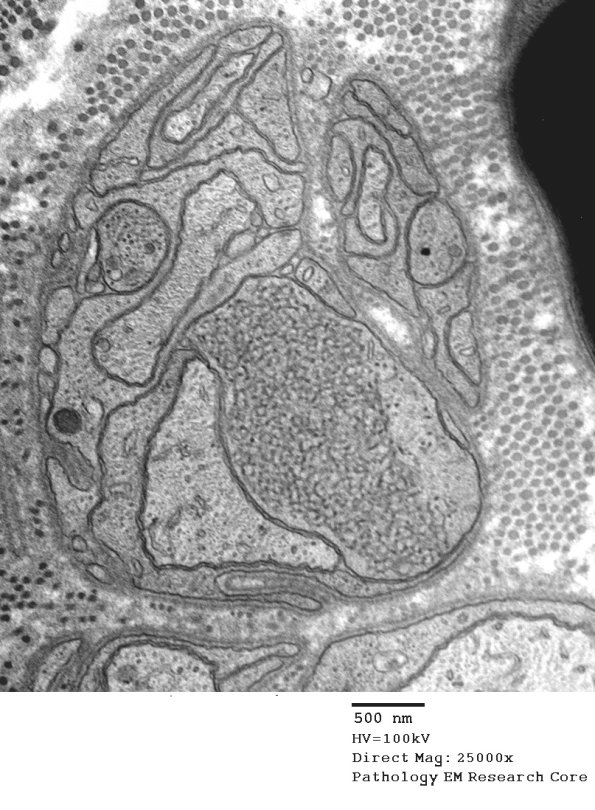

11I1,2 This is a collection of Schwann processes and a growth cone or two. (electron micrographs)